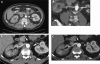

Spontaneous renal artery dissection (SRAD) is a rare event, and thus may be a challenge for physicians to diagnose and treat. We report a case of SRAD in a healthy 56-year-old male who presented with flank pain, fever, and elevated white blood cell count. The patient was initially diagnosed with nephrolithiasis versus pyelonephritis and was admitted for observation. Multiple imaging modalities, including non-contrast computed tomography (CT), magnetic resonance imaging (MRI) with gadolinium, CT angiogram, and intraoperative angiogram, were used to make the final diagnosis of SRAD. The patient was treated with endovascular stent placement and is currently free of pain with normal laboratory values and blood pressure.